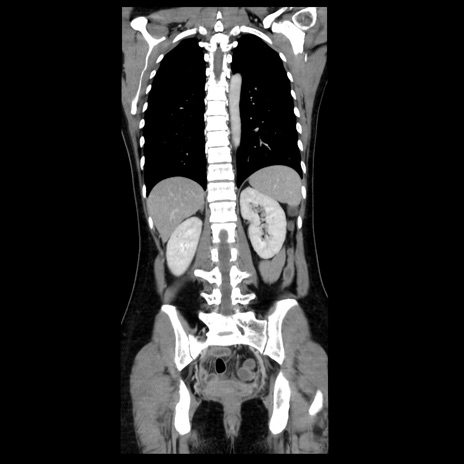

症例39(冠状断像)

【症例】40歳代女性

【主訴】上下腹部痛

【現病歴】2日目から下腹部痛あり。夜間は痛みで眠れなかった。昨日より上腹部痛と下痢が出現。臥位で痛みは軽快したため、休んでいた。本日になって臥位でも立位でも痛みが強くなってきたため救急要請。

【既往歴】子宮内膜症

【身体所見】部:平坦・軟、左上下腹部に圧痛あり、反跳痛あり。

【データ】WBC 21800、CRP 26.78

CT